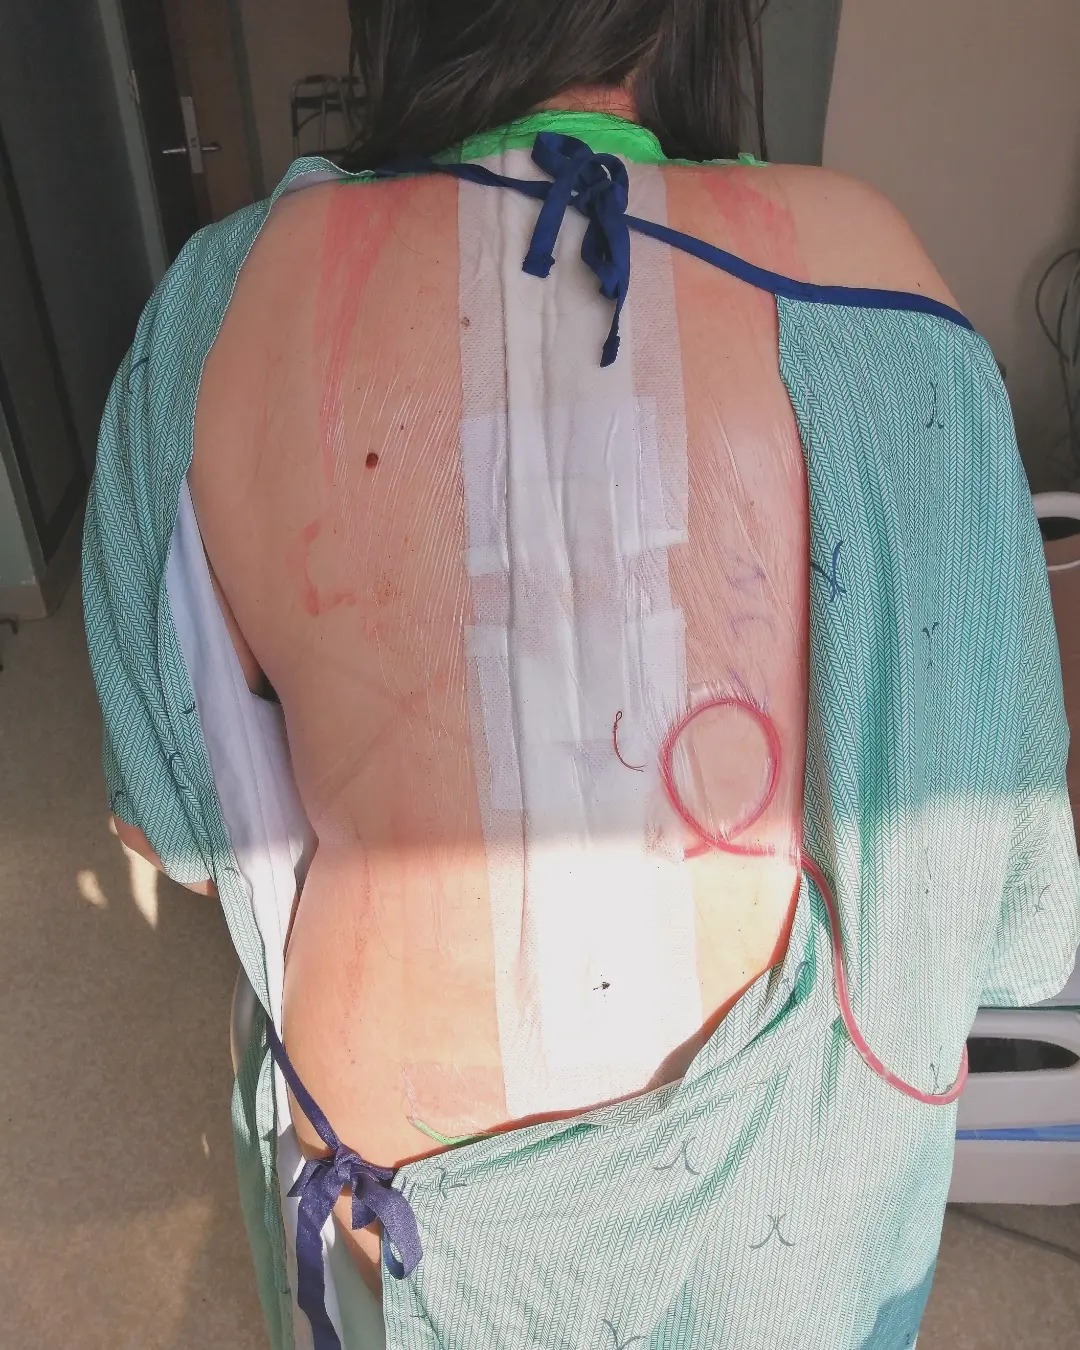

In March 2024, I underwent my second extensive spinal fusion from t2-l3 where unfortunately, my dominant arm became paralyzed. During recovery, I also developed rebound pulmonary emboli and some screws in my spine became misaligned from pushing myself too hard, too soon.

In May of 2025, I also underwent a nerve and muscle transfer surgery to try to regain back some nerve function in my paralyzed right arm and hand. Again, I had complications with rebound pulmonary emboli and had to be rushed back into surgery for compartment syndrome and a ruptured artery to avoid amputation. Content warning for graphic medical image below.

I've since healed from these surgeries and after meeting with my spine surgeon this week, we've made plans for a third, urgent revision spinal fusion for this upcoming October. I will have my existing fusion extended from t2-l3 to t2-l5 (or t2-pelvis) to address nerve injury in my lower spine under the existing hardware from degeneration related to my disease. The misaligned screws in the thoracolumbar region will be replaced and my two large paraspinal rods will also be removed and replaced with even longer ones.